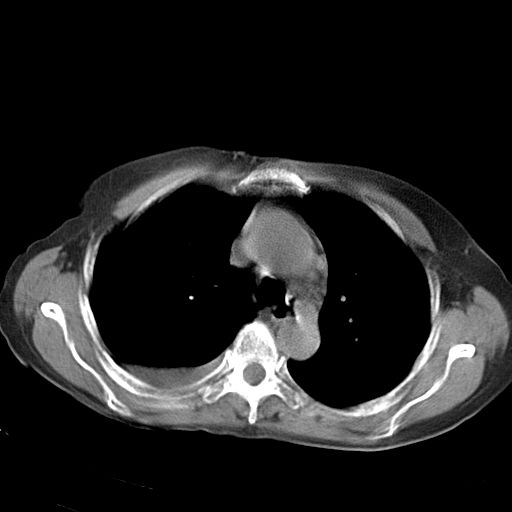

以下是引用jiazh在2006-12-7 20:37:00的发言:[br]肝脏周围半狐形低密度影,肝脏表面受压推移,考虑膈下脓肿可能性大;2、右侧胸腔积液

以下是引用拾荒者在2006-12-7 21:44:00的发言:[br]肝内外胆管多发结石,右膈下多发脓肿,右胸膜腔及叶间裂积液,左肾囊肿。[br] [br]